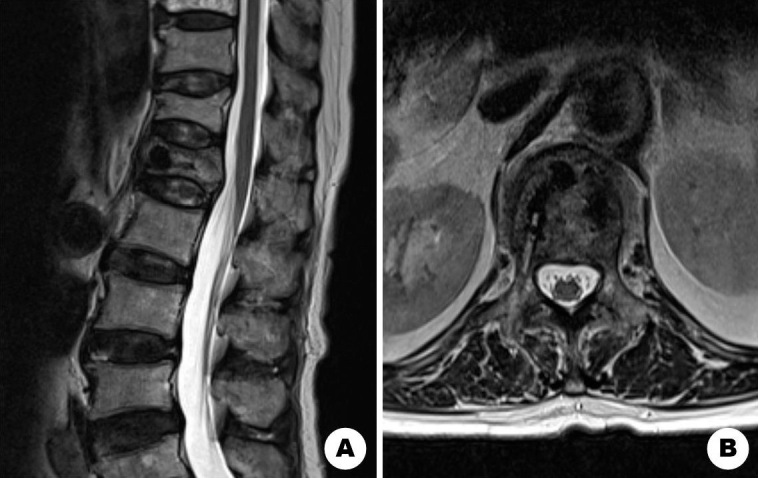

Complete Resolution of Hematoma after Vertebroplasty in Epidural Hematoma Associated with Acute Osteoporotic Vertebral Fracture: A Case Report.

急性骨质疏松性椎体骨折伴硬膜外血肿椎体成形术后血肿完全消退1例报告。